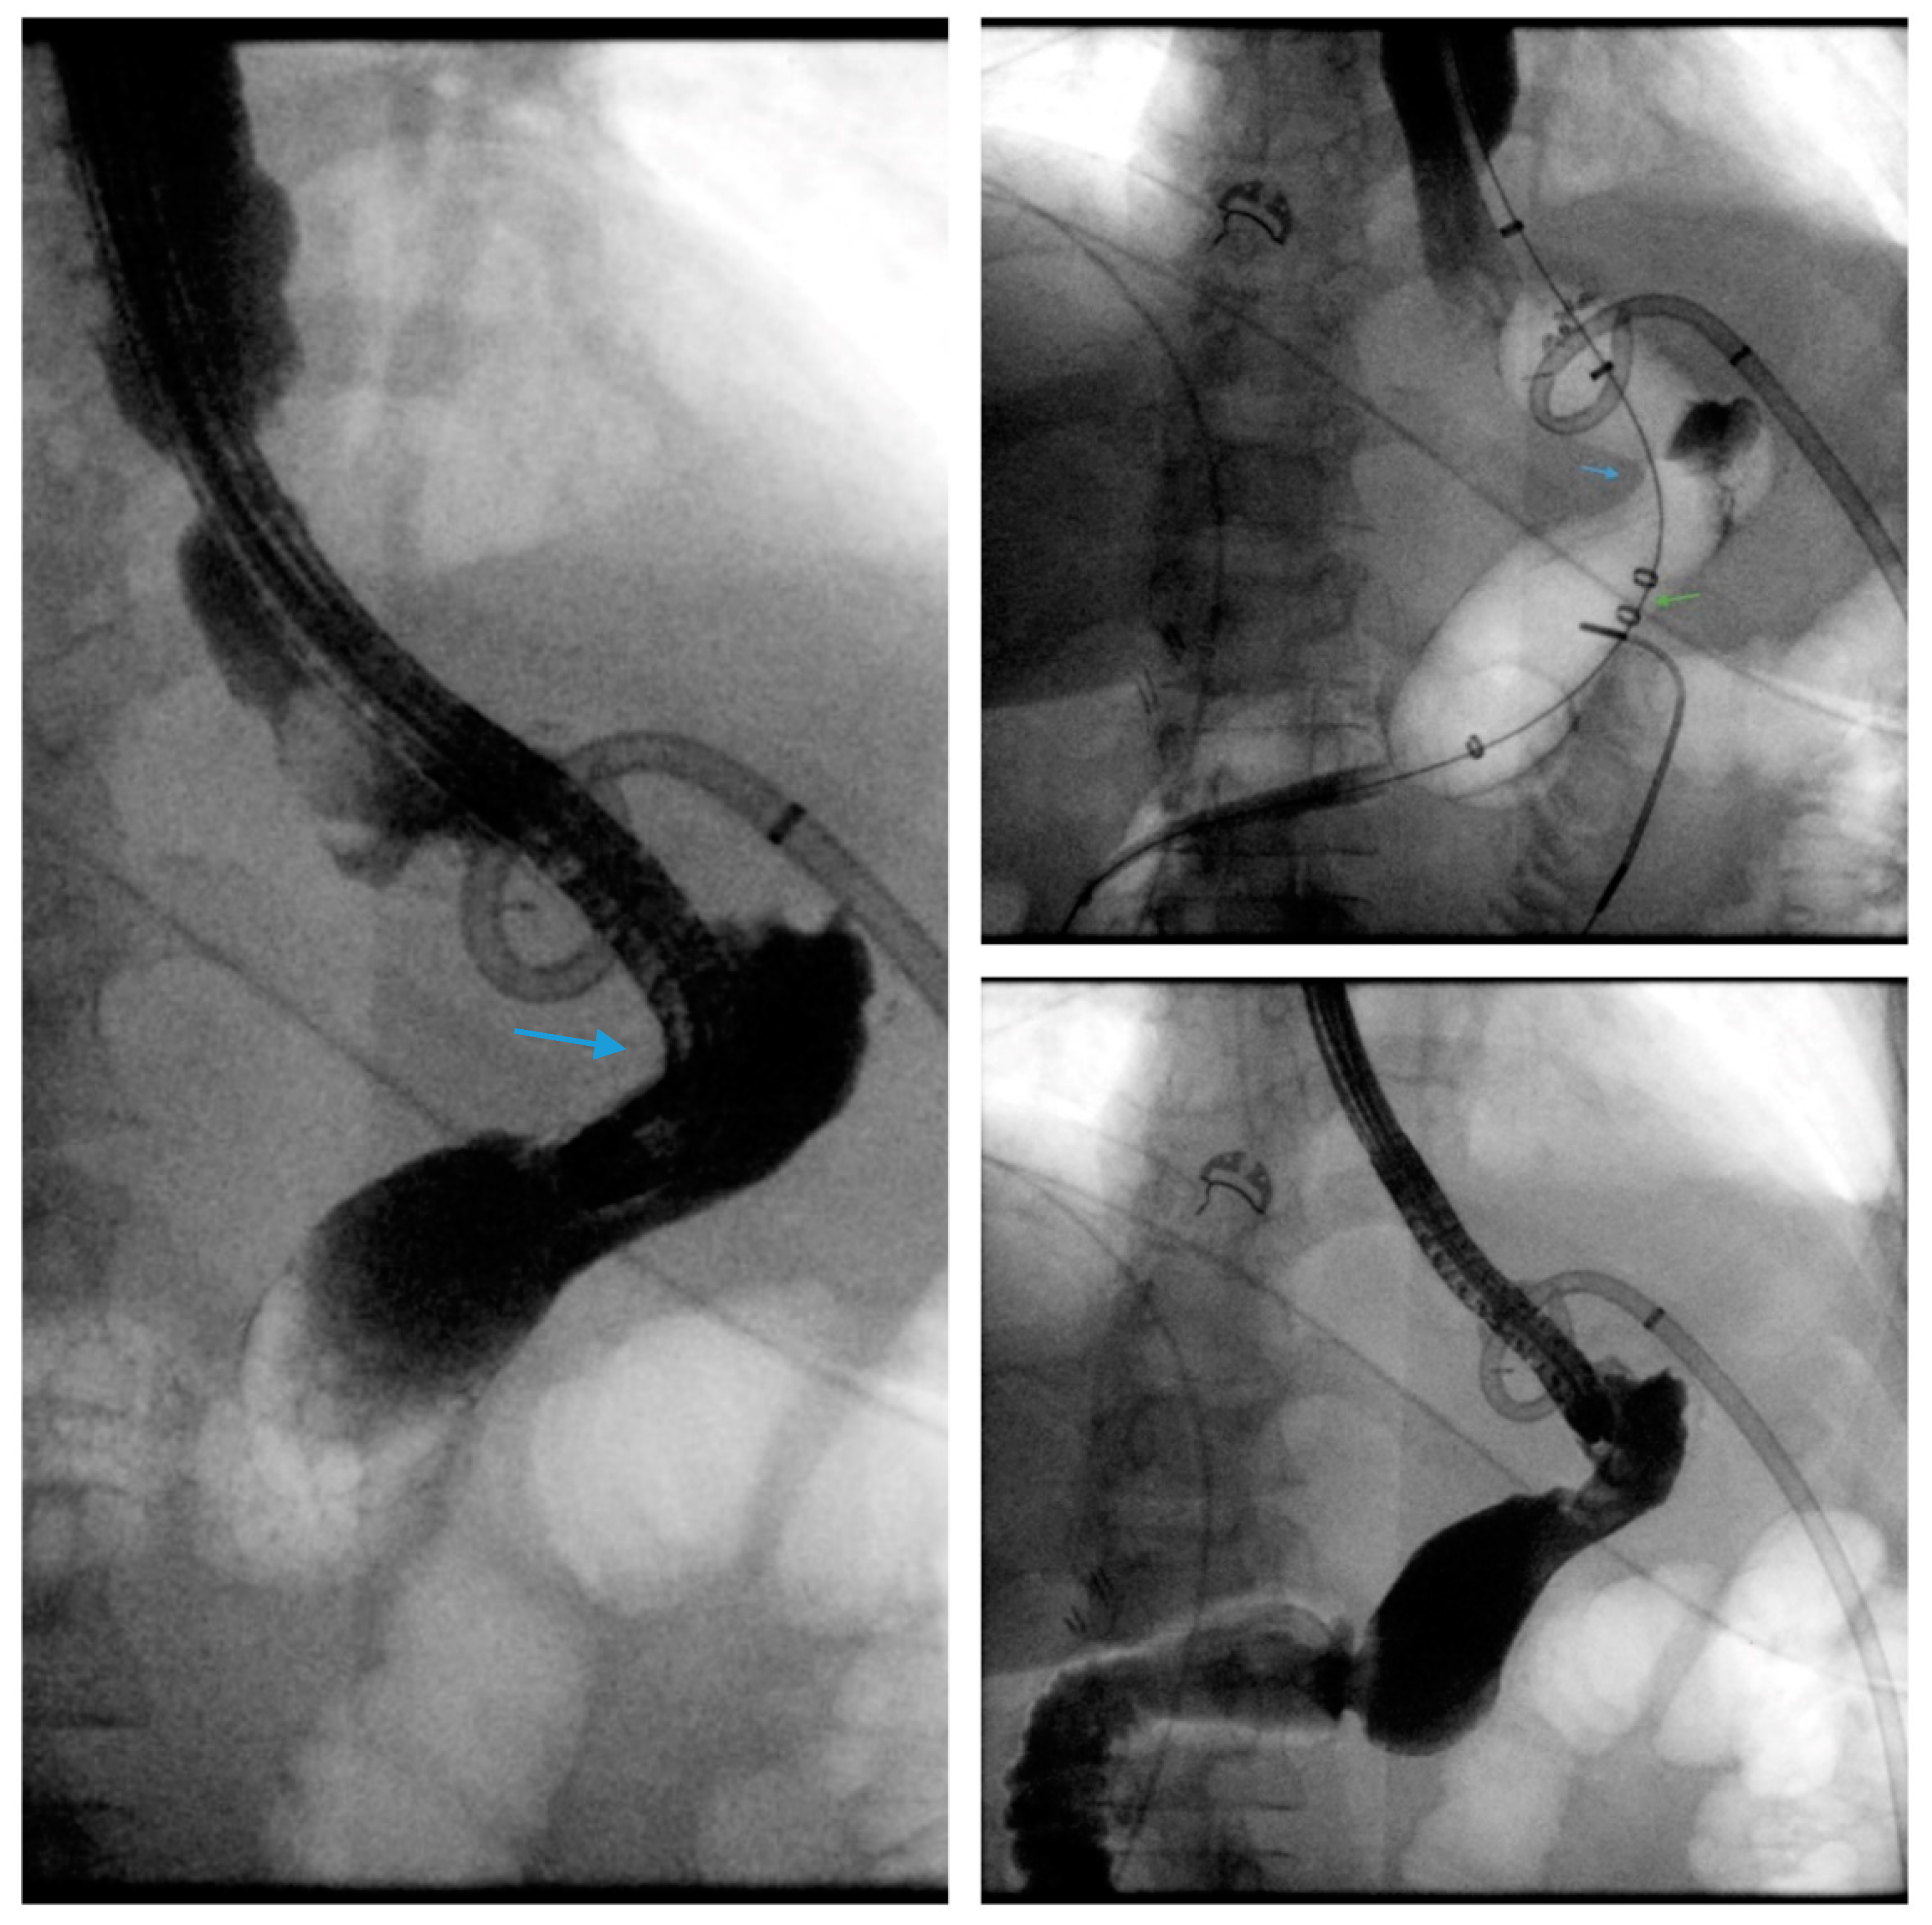

3.8. Endoscopic Septotomy

- Campos, J.M.; Ferreira, F.C.; Teixeira, A.F.; Lima, J.S.; Moon, R.C.; D’Assunção, M.A.; Neto, M.G. Septotomy and Balloon Dilation to Treat Chronic Leak After Sleeve Gastrectomy: Technical Principles. Obes. Surg. 2016, 26, 1992–1993. [Google Scholar] [CrossRef] [PubMed]